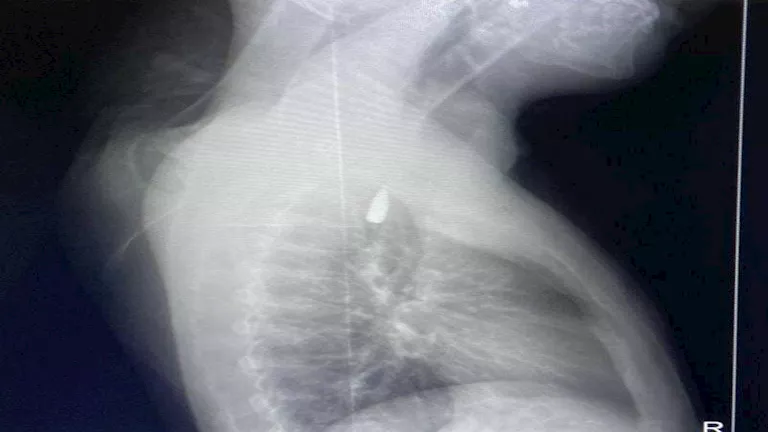

كان المريض الفلسطيني، تعرض لإصابة بطلق ناري في الرأس منذ فترة، استقر المقذوف على إثرها داخل تجويف القفص الصدري قرب الشريان الأورطي، وهو أكبر وأهم شرايين الجسم والمسؤول عن تغذية جميع الأعضاء الحيوية.

وأوضح الدكتور تامر عبد الله، عميد كلية الطب جامعة الإسكندرية، ورئيس مجلس إدارة المستشفيات الجامعية، أنه رغم دقة الحالة وتعقيدها إلا أن الفريق الطبي نجح في استخراج المقذوف بأمان بعد عملية جراحية نادرة.

وأشار إلى أن العملية استمرت عدة ساعات داخل المستشفى الجامعي الجديد، حيث خضع المريض بعدها للرعاية الطبية اللازمة، وحالته حاليًا مستقرة وتحت المتابعة الدقيقة من الفريق المختص.